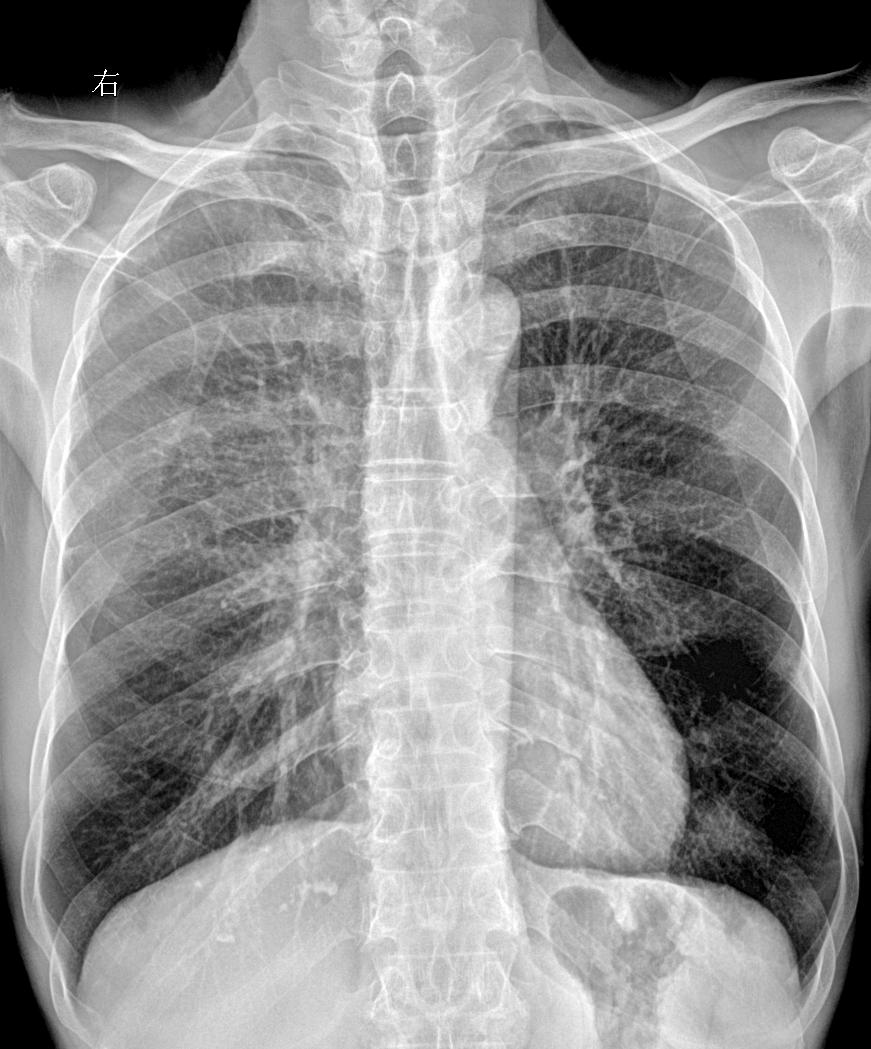

胸闷气短